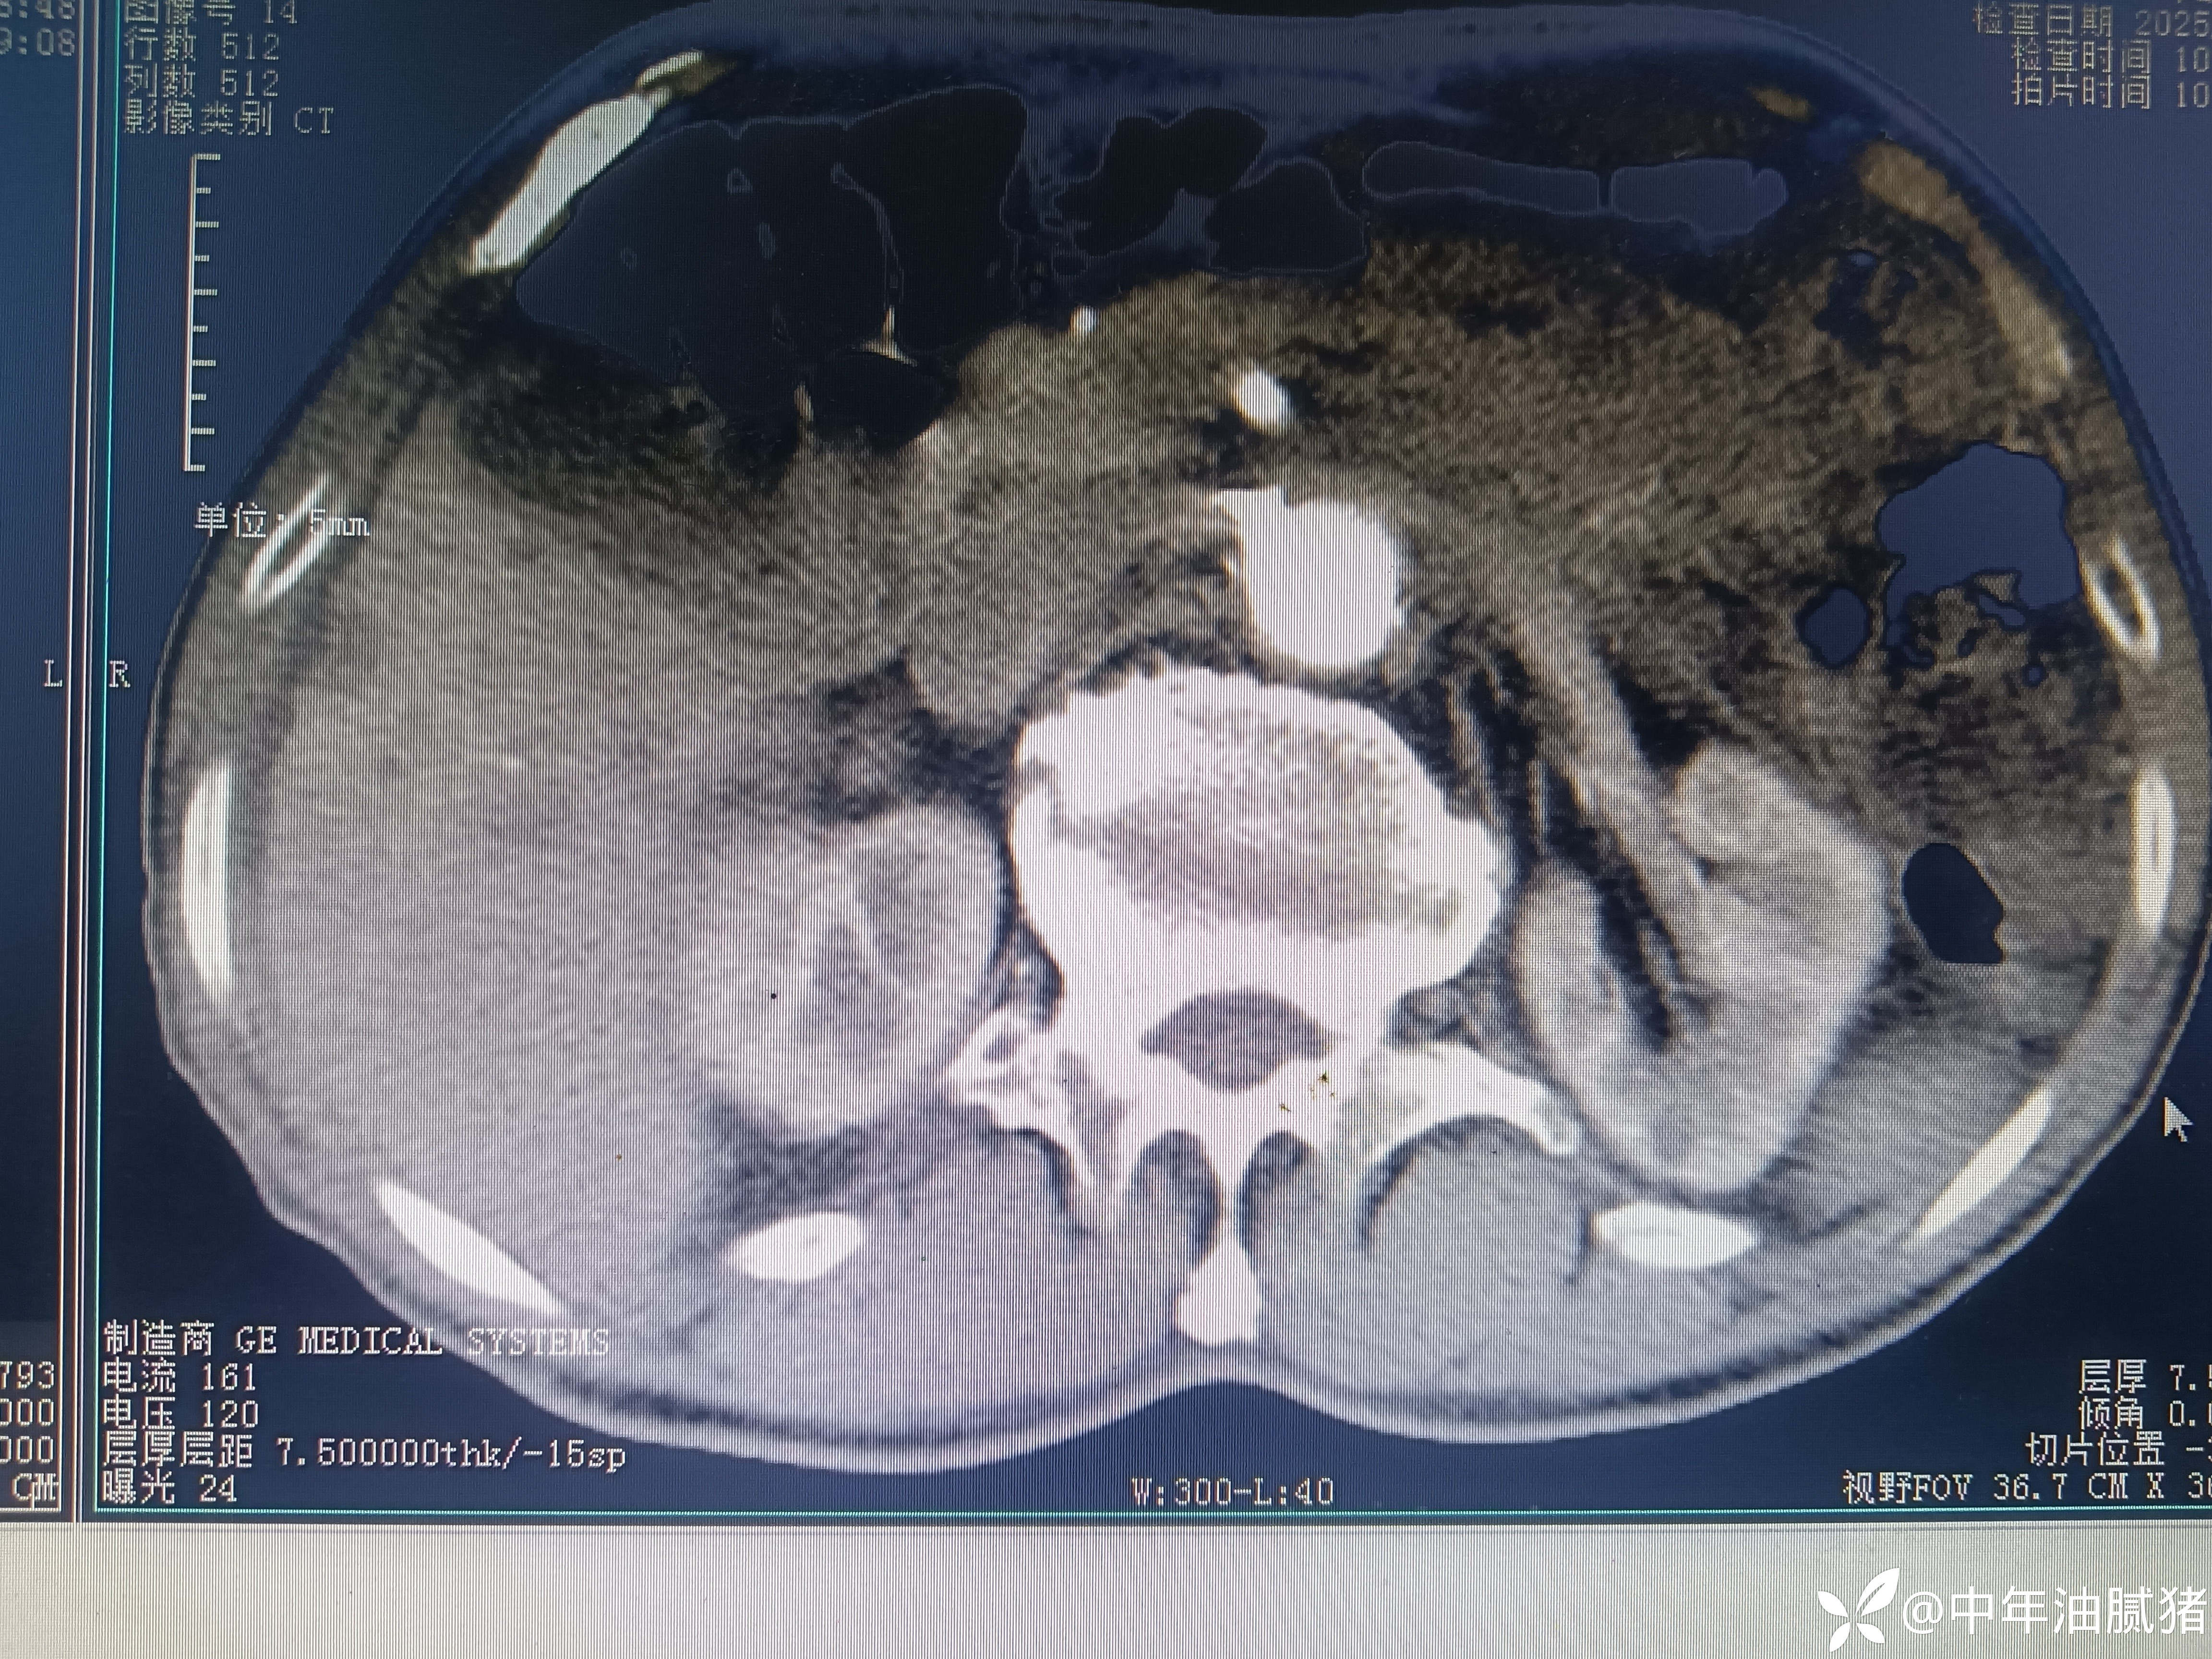

肺ct看到肝内病灶,行增强检查

建议增强ct.报告如下

看后,我隐隐约约觉的不是肝囊肿那么简单?元芳,你怎么看?狄阁老,我也是这么认为!摇人,掏起手机:喂,w主任,请帮我看看这个ct。5分钟后报告修改如下